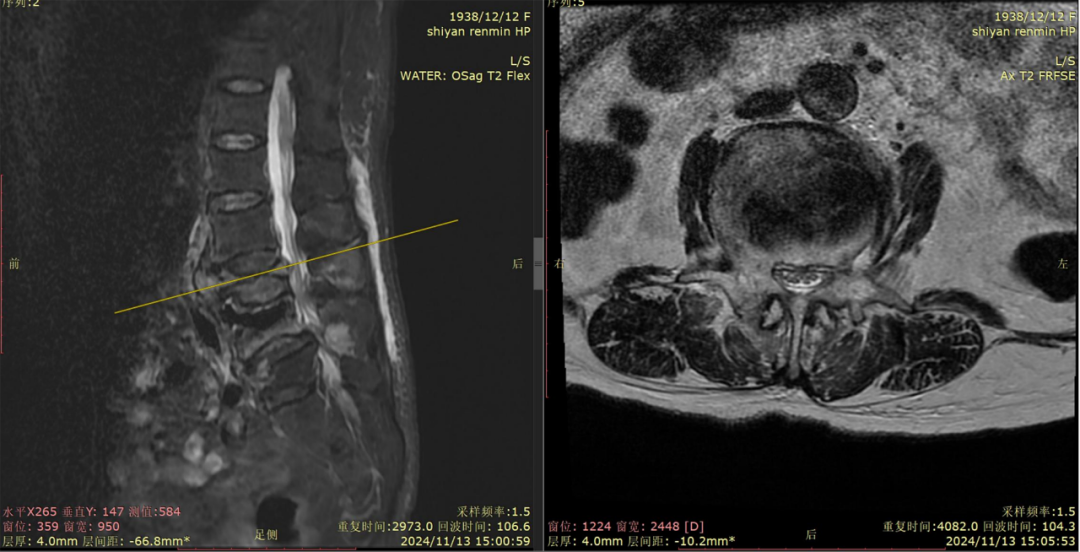

历经三个半小时,手术顺利完成。术后当晚,张奶奶就表示,腰疼明显好多了,可以独自翻身,腿也灵活了。

▲术后磁共振、X片

经过进一步康复治疗,又过了两天,张奶奶已经可以独自下地走路了,如同重获新生。她对曾小军的技术赞不绝口,对医护人员的照顾感激不尽。